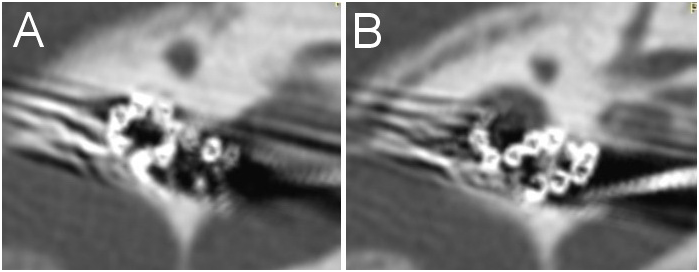

There was 7 cases of a labyrinthine ossification. We performed an implant removing and implantation new device (through second turn) and simultaneously CI at the second ear. The surgical approach was as follows: extended mastoidectomy with exposure of sigmoid sinus, dura mater and sinodural angle. After extended posterior tympanotomy up to the facial nerve canal wall and removal of the incus and bony bridge the first cochleostoma was created in the typical place (with drilling of the basal turn up to its passage into the ascending part taking into consideration risk of internal carotid artery damage). Then the second cochleostomy was performed 1 mm inward to the anterior margin of the oval window niche on the line proceeding from the processus pyramidalis parallel to the stapes crura after removal of the anterior crus of stapes and anterior 2/3 of the footplate. The posterior stapes crus and tendon of stapedial muscle was preserving intact. The insertion of the electrode array was performed through second turn. A remain electrodes placed in exposed basal turn after removal of the part promontory wall separating the basal and the second turn (Figure 2).

Figure 2 CT of left temporal bone. A – Electrode array in second turn. B ‒ Remain electrodes placed in exposed basal turn after removal of the part promontory wall separating the basal and the second turn.